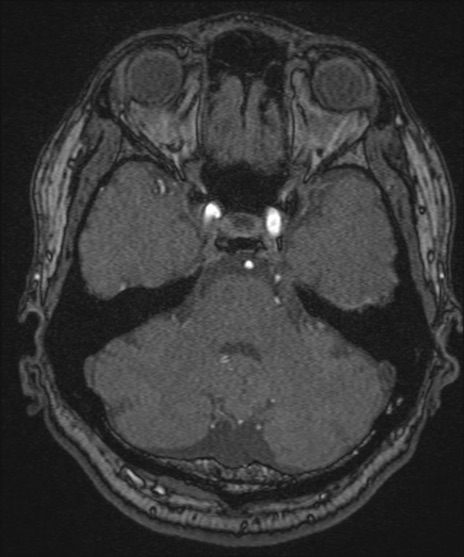

【頭部】TIPS症例12 MRI(MRA元画像)

【症例】40歳代男性

松果体にあるものはなに?